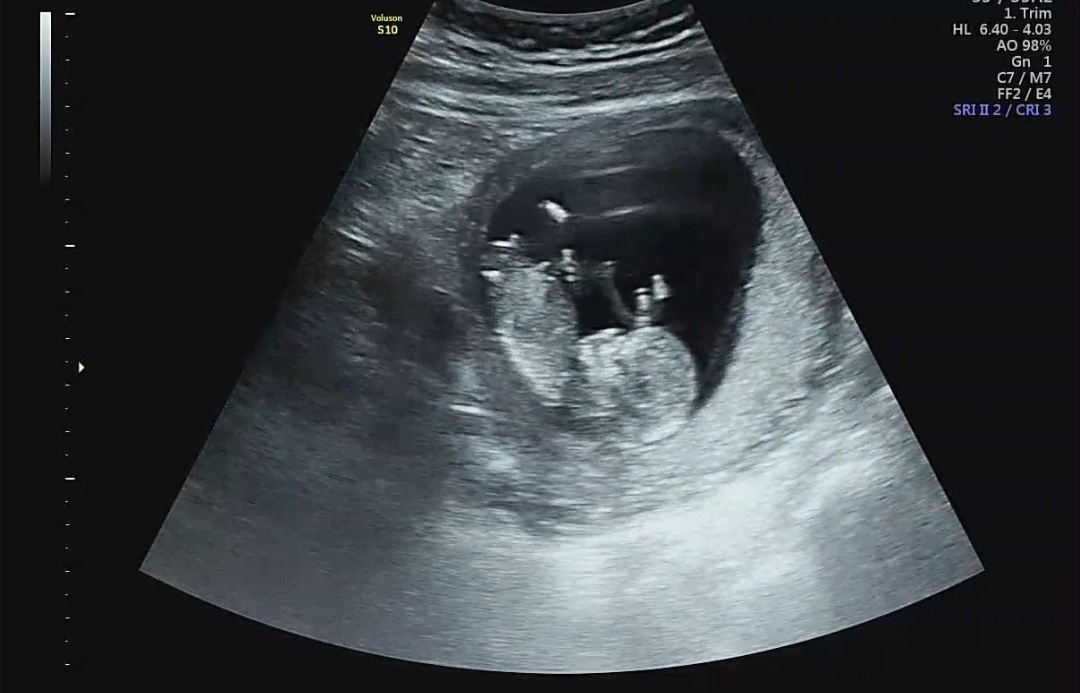

12주 1일 각도법 아들맞나요?

저기 튀어나온 저게 생식기 맞는지 모르겠아요